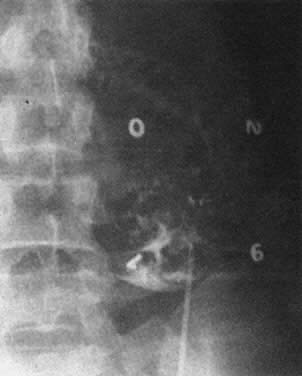

Ultrasound imaging techniques, introduced in the late 1970s, constitute a major advance in the management of maternal blood group alloimmunization.43 Ultrasound allows an estimation of placental and hepatic size and the presence or absence of edema, ascites, and other effusions (i.e., the presence or absence of hydrops fetalis; Fig. 11 and Fig. 12). Ultrasound is of great help in assessing fetal well-being (measuring the fetal biophysical profile), has increased the accuracy of placental localization, and has sharply reduced the incidence of placental trauma at amniocentesis.

Fig. 11. Sonogram of fetus with hydrops fetalis. Placenta is enormously thickened and edematous ( white arrow ). Fetal abdomen, which is grossly distended with ascitic fluid, is lateral to the arrow.(Bowman JM: Maternal blood group immunization. In Creasy RK, Resnik R (eds): Maternal-Fetal Medicine: Principles and Practice, pp 561–602. Philadelphia, WB Saunders, 1984)